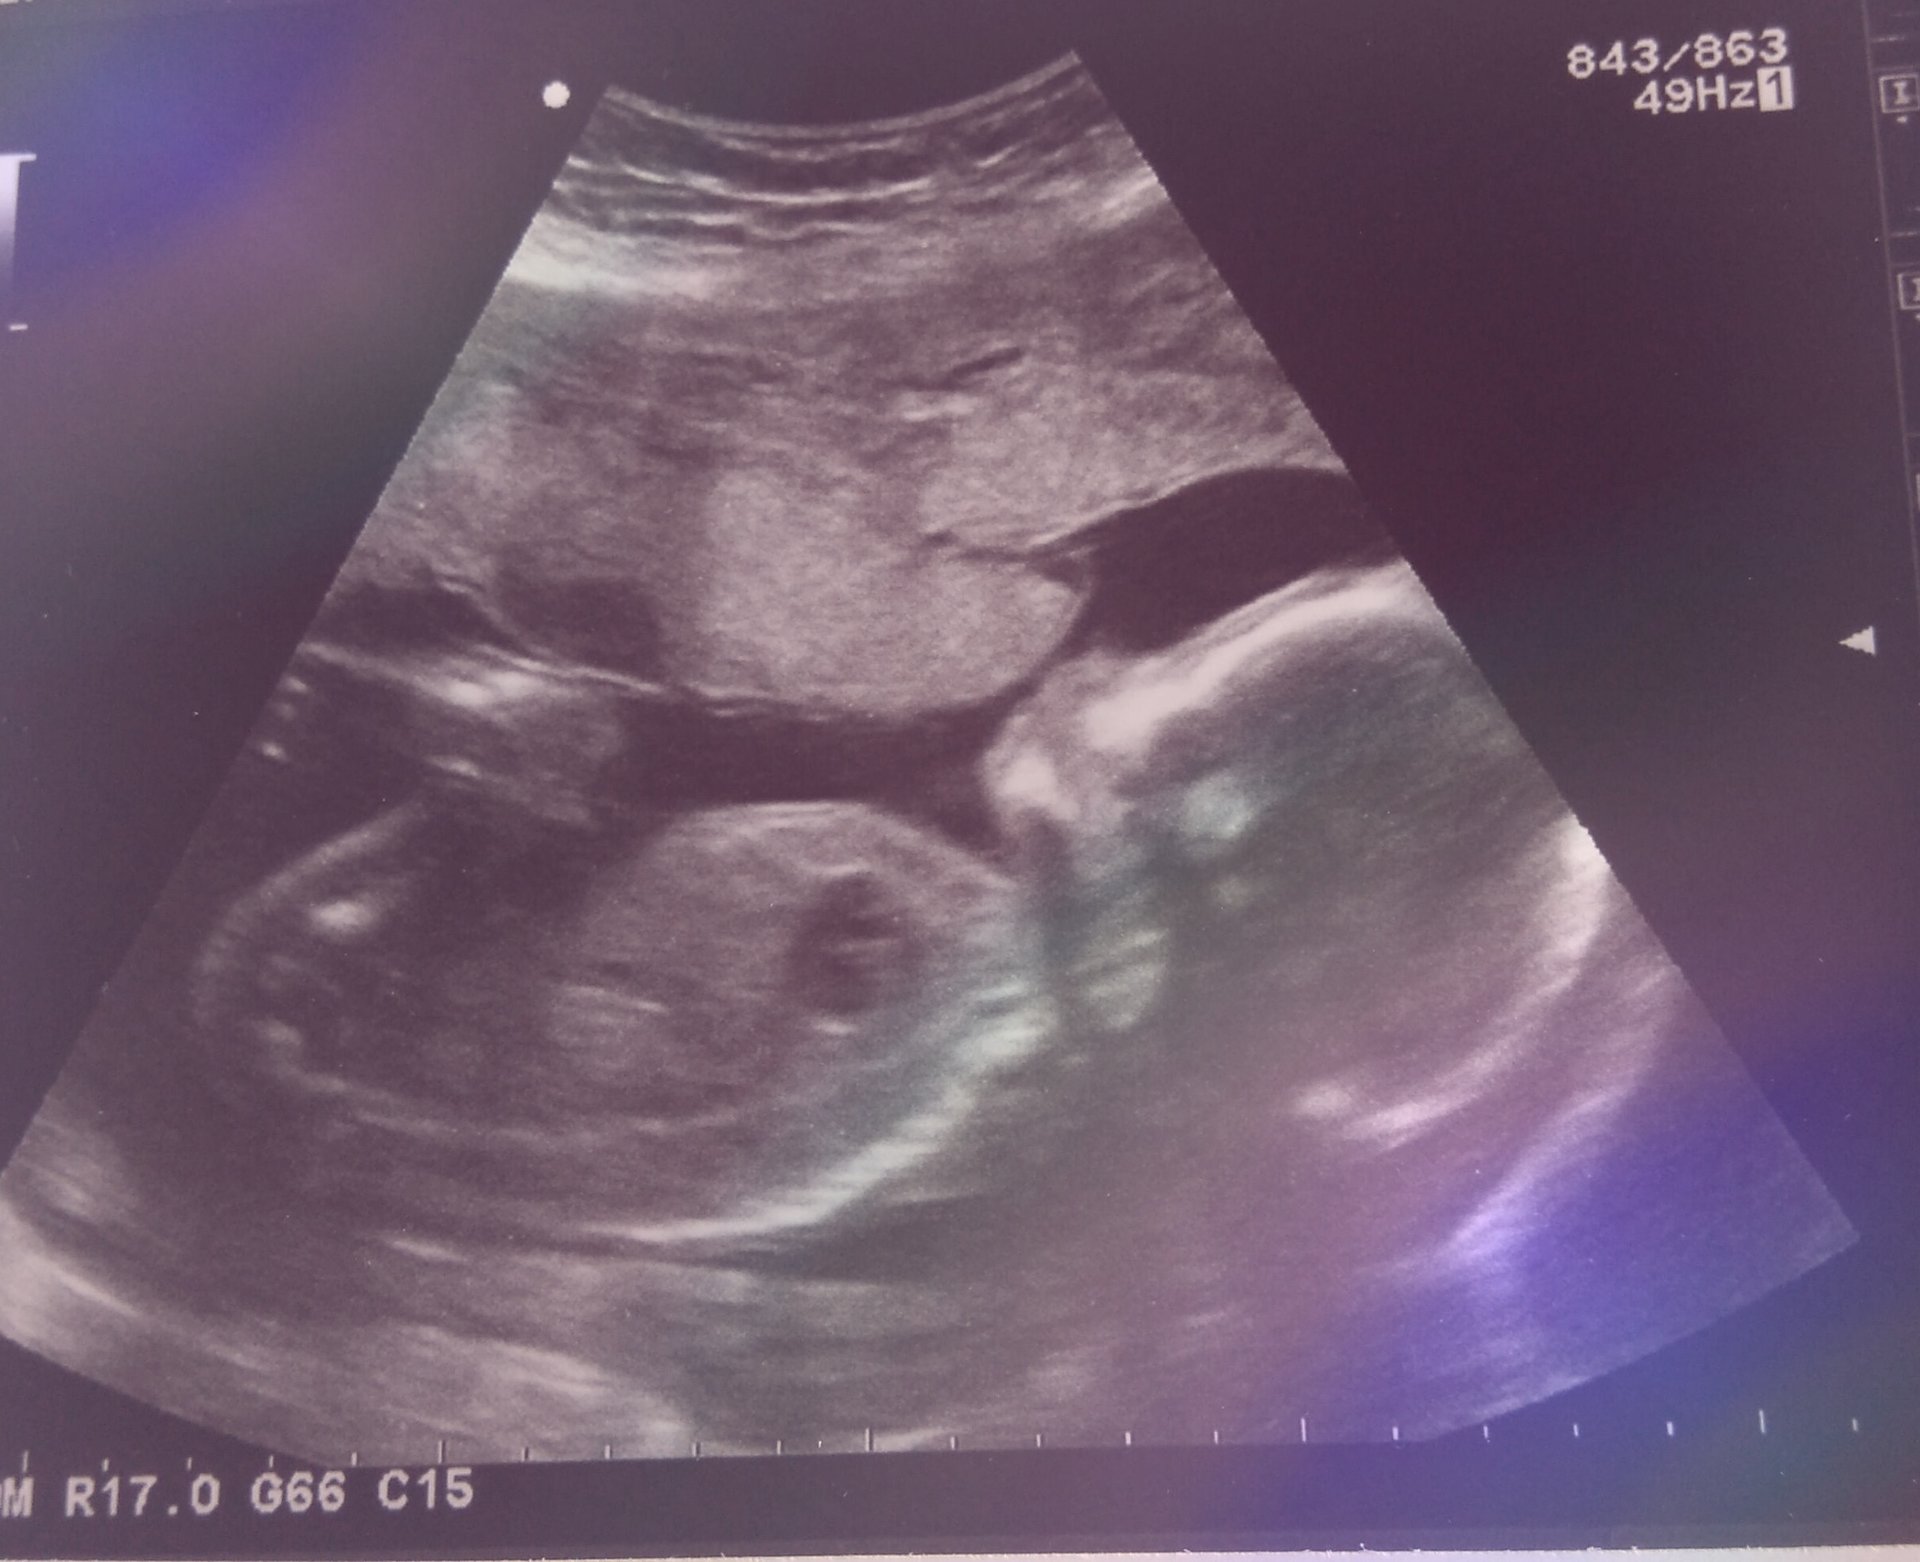

Can't believe I have a living breathing tiny human being inside of me! Baby was swallowing and putting hands on head. I also measured a week ahead! I also think I accidentally saw a penis when we are supposed to be team green! I am so excited!